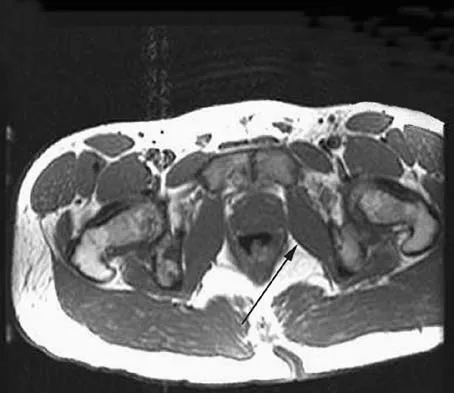

Question 51

An axial T1-weighted MRI scan of the pelvis is shown in Figure 13. The arrow is pointing to what muscle?

Explanation